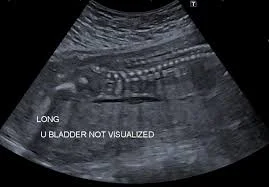

- Ultrasound